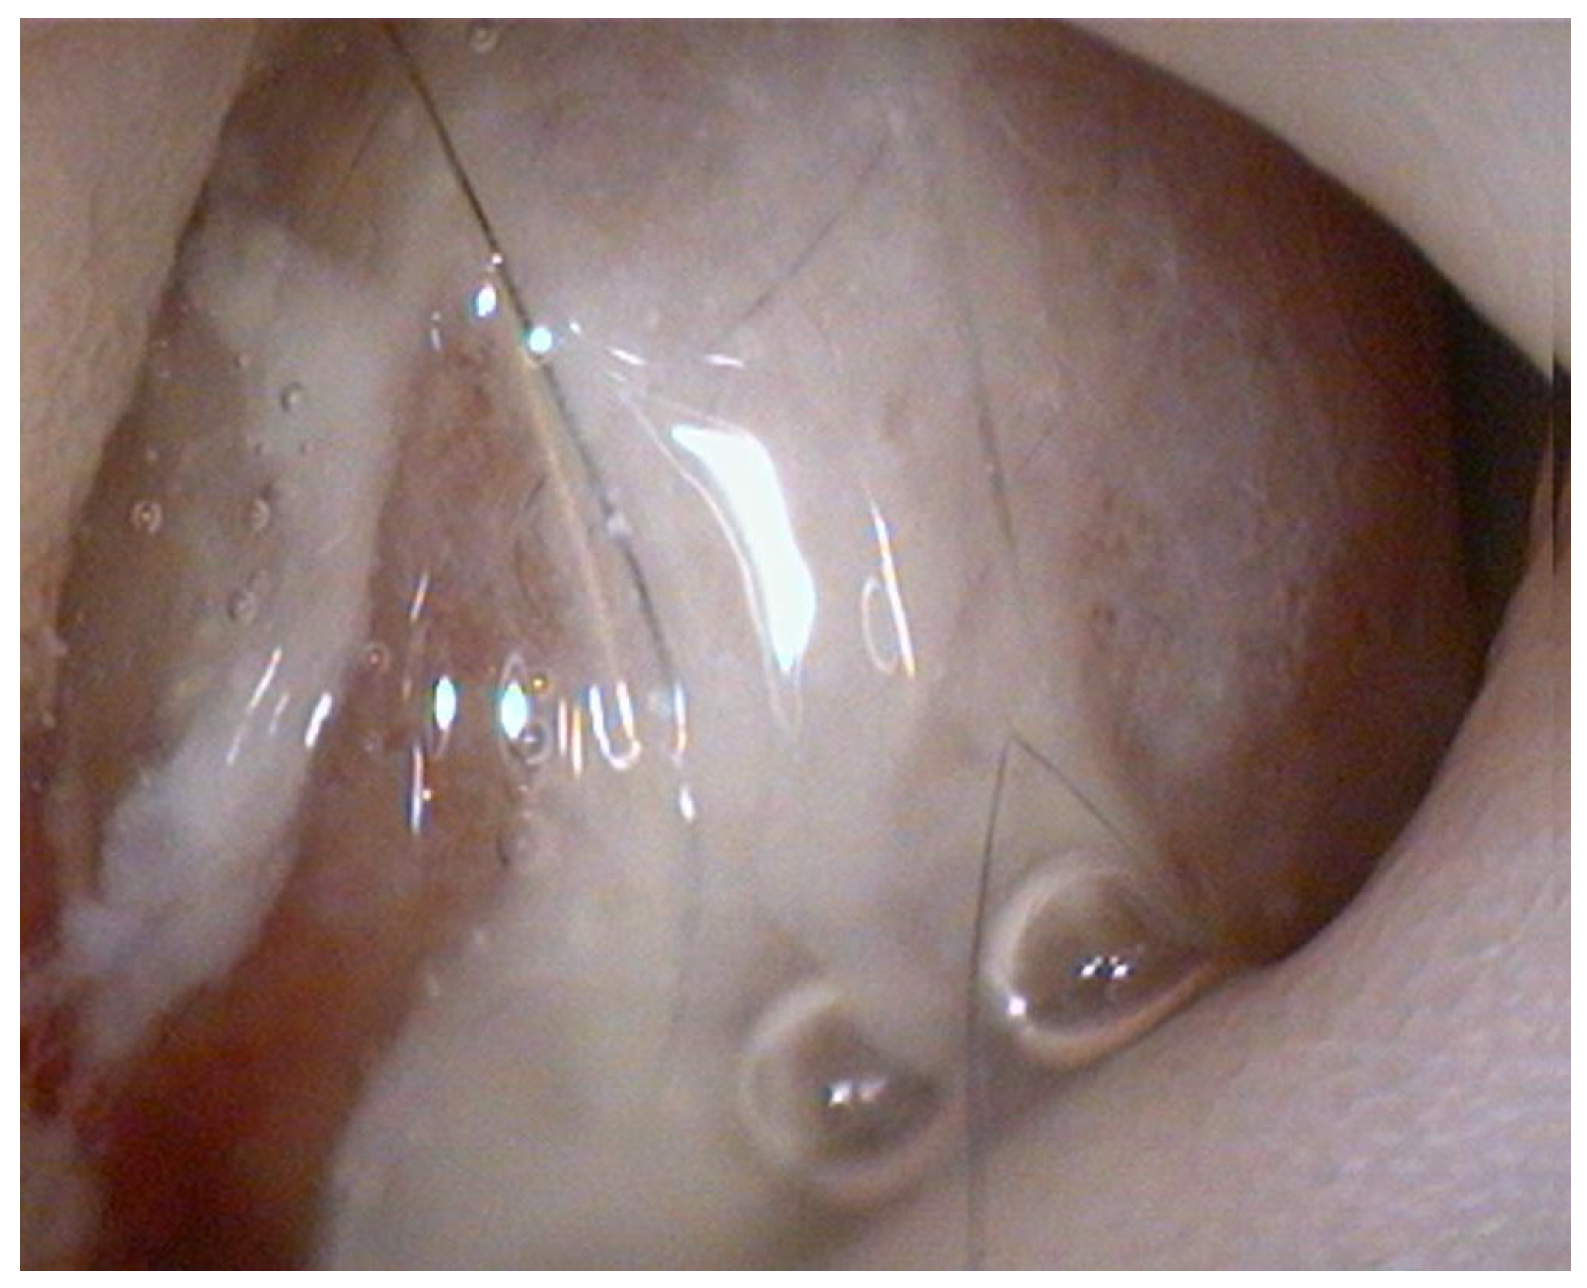

Endoscopy, performed using a flexible veterinary gastroduodenoscope (outer diameter 7.9 mm, Karl Storz Silver Scope 60714NKS), confirmed the presence of a submucosal sessile mass partially obstructing the duodenal lumen (Figure 1). It was not possible to fully advance the endoscope beyond the lesion for a complete duodenal evaluation; however, the mucosa visible just distal to the mass displayed shortened and edematous villi. Thanks to the small diameter of the biopsy forceps, it was possible to pass beyond the lesion endoscopically and obtain samples from the duodenal tract immediately distal to the mass. Additional biopsies were taken from the mass itself and from the gastric mucosa, which showed diffuse follicular hyperplasia, using 2.4 mm fenestrated biopsy forceps (Alton AF-D2421BT).

Histopathological examination of the gastric biopsies revealed mucosa with deep, hyperplastic crypts and occasional erosive and ulcerated areas replaced by necrotic and collagenous material containing abundant eosinophils, together with a mixed inflammatory infiltrate of neutrophils, small lymphocytes, and scattered eosinophils. Duodenal biopsies, including those obtained distal to the mass, showed irregular, shortened and fused villi with a moderate mixed lymphoplasmacytic infiltrate containing neutrophils and eosinophils in the lamina propria. Histopathological examination of the duodenal mass revealed a sample devoid of recognizable microanatomical architecture, composed of fibrocollagenous tissue interspersed with densely cellular areas (Figure 2). Overall, the findings were consistent with eosinophilic and fibroplastic gastroenteritis compatible with feline gastrointestinal eosinophilic sclerosing fibroplasia (FGESF).

Figure 1. Endoscopic view of the duodenal mass.